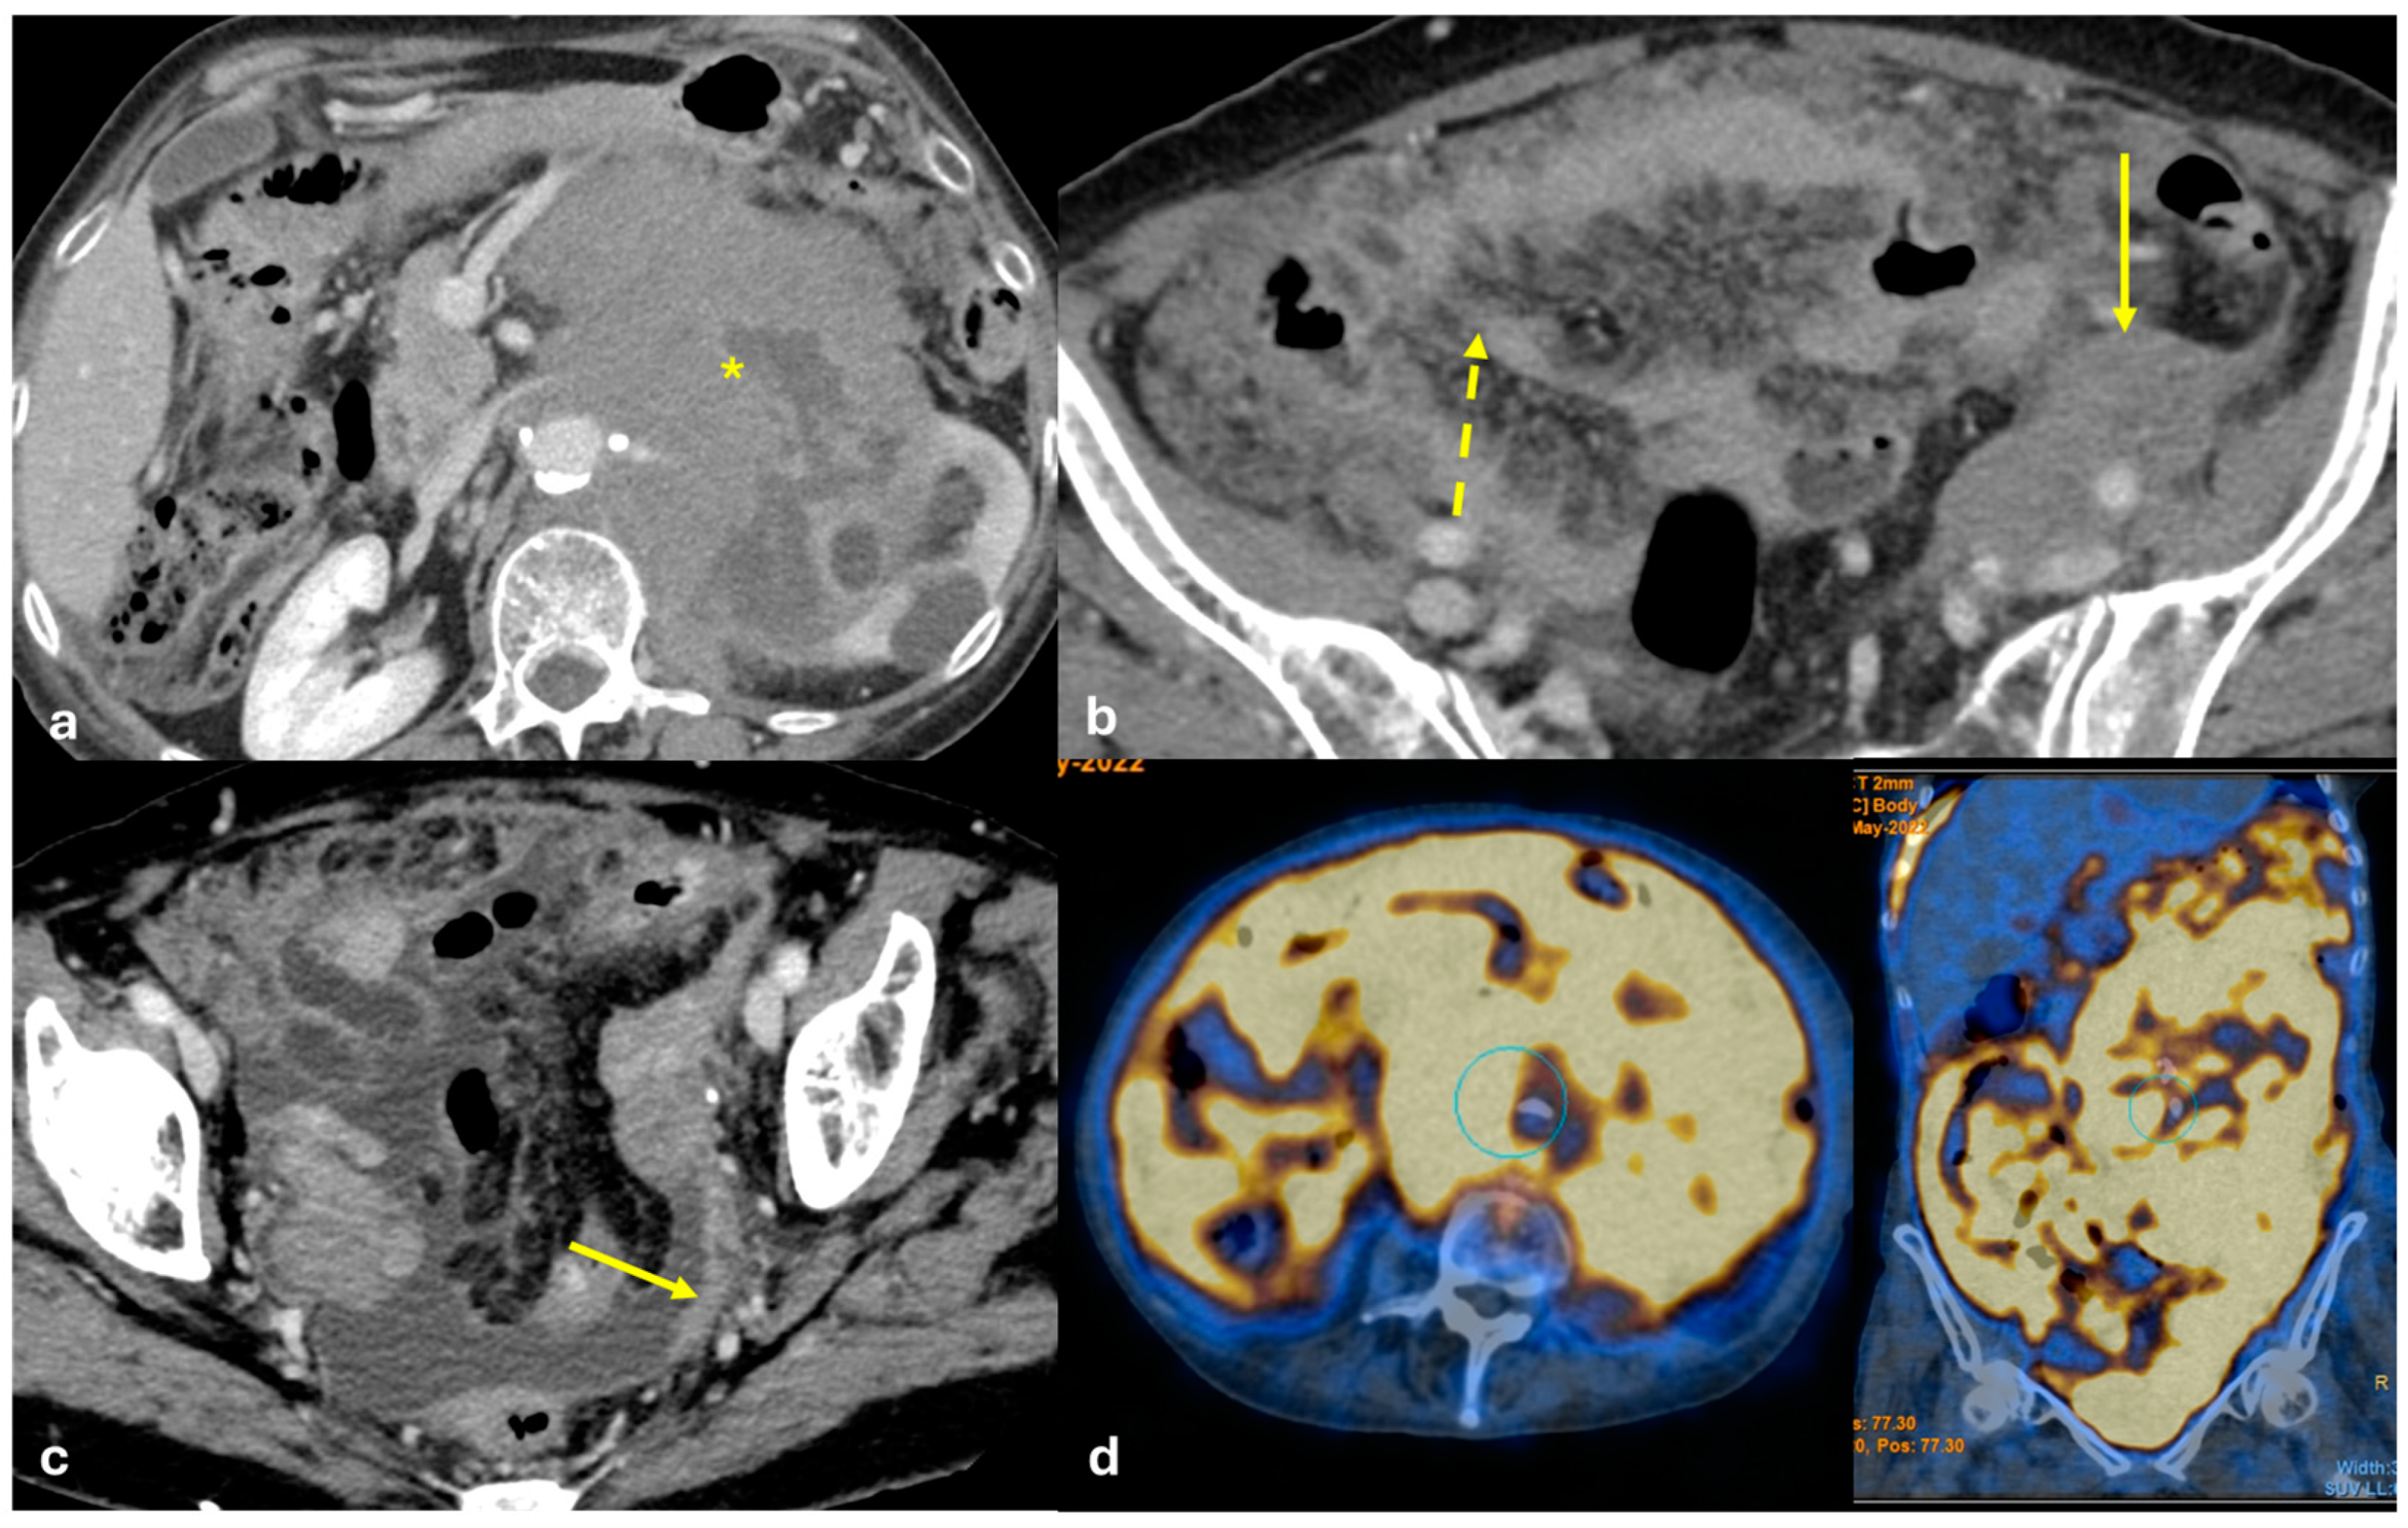

- Micro-nodular pattern: micro-nodules with a diameter ≤ 5 mm (Figure 1);

- Nodular pattern: nodules with a diameter > 5 mm (Figure 2a);

- “Omental cake”: nodular thickening of the omentum (Figure 2b);

- Plaque pattern: confluent nodular plaques, typically involving the lower surface of the right diaphragm (Figure 3);